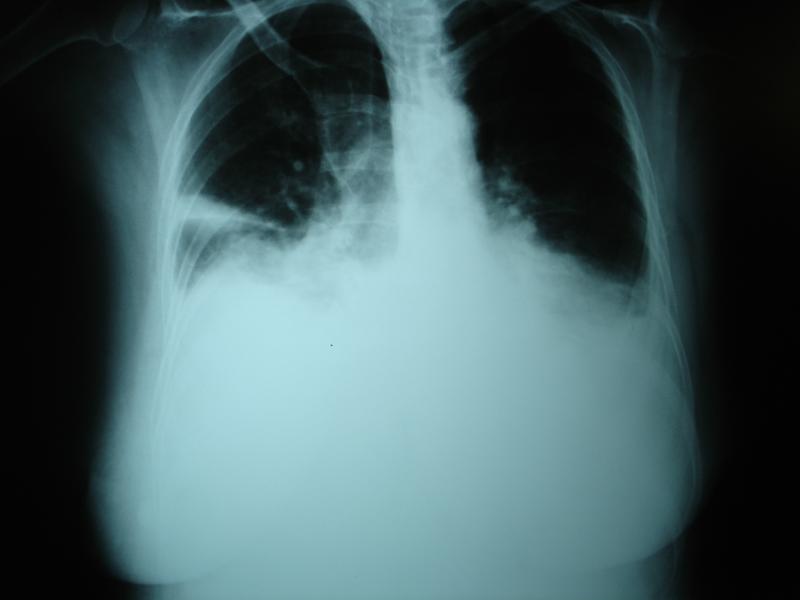

The study included 135 patients (median age 81 years, 33 percent female) with acute heart failure, left ventricular ejection fraction ≤45 percent (median 25 percent), and non-negligible pleural effusion. None of them had very large effusions (more than two-thirds of the hemithorax).

Overall, around half of the population had new-onset heart failure (53 percent) and received anticoagulation therapy (49 percent). Most participants underwent different imaging procedures as part of their diagnostic workup before randomization. Computed tomographic scan results were available in 22 percent of participants, ultrasound results in 46 percent, and chest X-rays in 84 percent. Pleural effusion was bilateral in 73 percent.